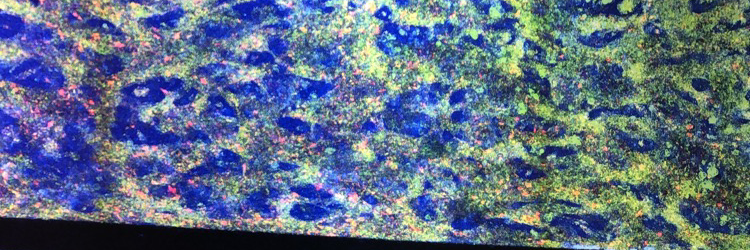

Thrilled to share that our review "Biomaterials for Personalized Cell Therapy" is now available online in #AdvancedMaterials! @LisaRVolpatti @AdvSciNews @kochinstitute

Scientist at Pyxis Oncology | PhD from @MITDeptofBE Langer and Anderson labs @kochinstitute